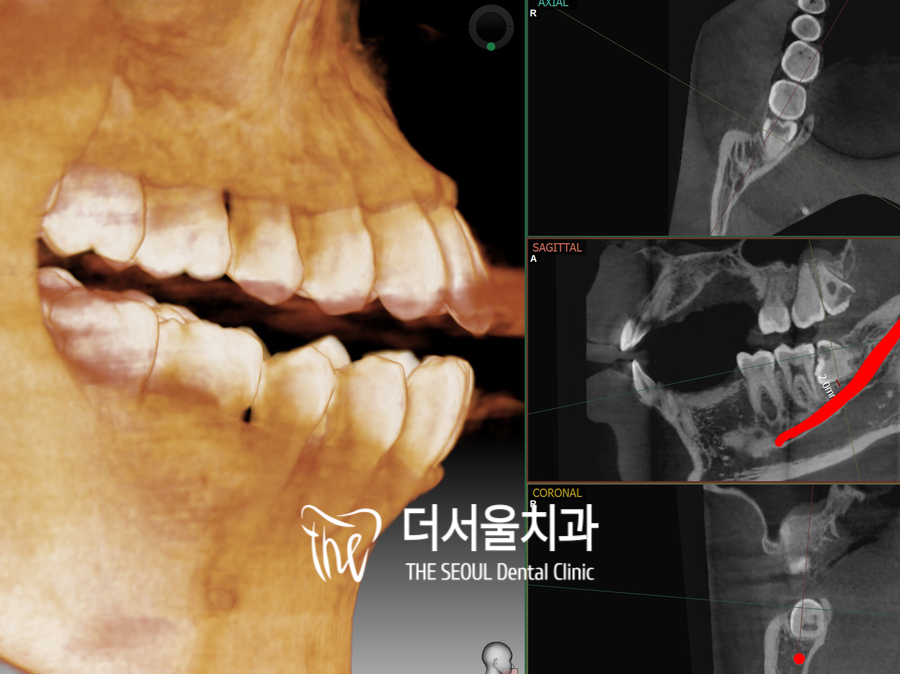

안녕하세요, 더서울의 박현준 원장입니다. “ 어려운 사랑니 , 예를 들어 어떤 것들을 꼽을 수 있을까요? ” 네, 그간 더서울에서 여러